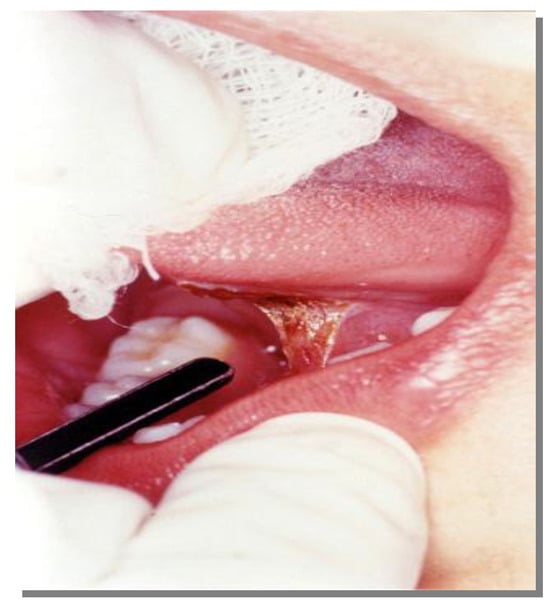

Step 3 - The laser was applied perpendicular to the lingual frenum so that it was sectioned in the shape of a lozenge. Subsequently, the edges were vaporized with the same potency to obtain a better contour. The surgeon stretched the tongue upwards during the application so that the depth of incision could be controlled and the procedure facilitated as shown in Photographs 02 and 03.

Figure 2.

Frenectomy procedure assisted by CO2 laser.

Figure 3.